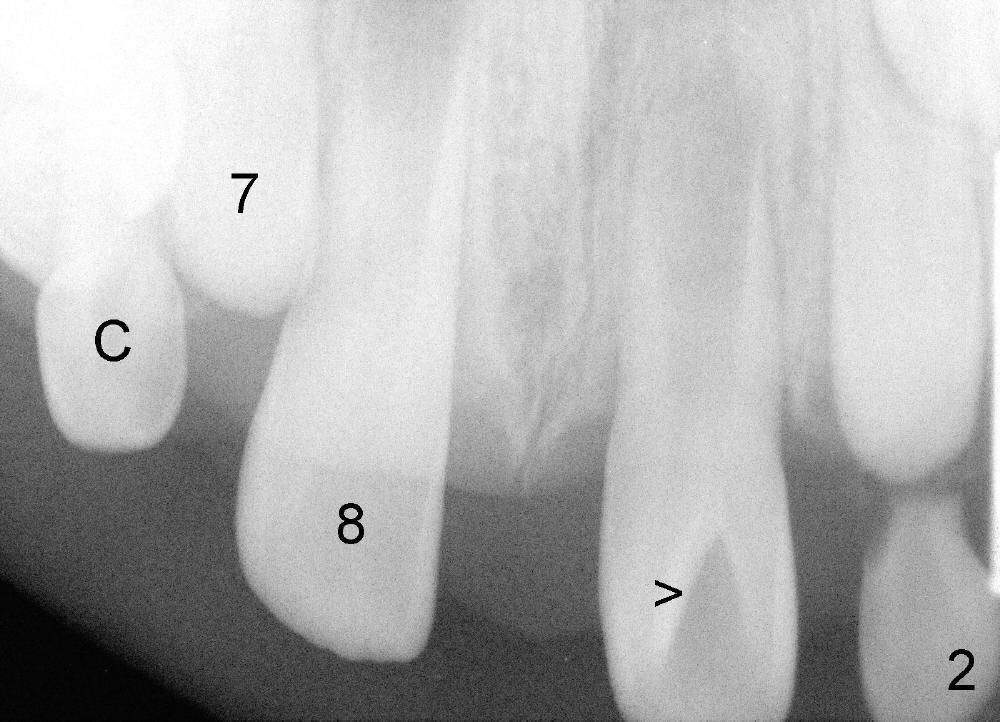

A seven-year-old co-operative boy presented to my office for composite. Exam shows open bite and a large diastema between the erupting upper central incisors (Fig.1-4). His mother notices that the diastema is more due to lateral displacement of the right central than the left central's (compare to Fig.1: black dashed line). She asks whether the uneven displacement will interfere with eruption of the upper right lateral incisor (Fig.2,3, as compared to Fig.4). She is interested in early ortho.

There are three questions. Will the right lateral erupt by itself and the diastema self corrects? When can we start ortho? How can we treat deep cingulum of #9 (Fig.2 >), removing marginal ridges or placing composite in the cingulum? The purpose of cingulum treatment is to prevent caries. Do we also need to add composite to #9 proximal surfaces to make it look as wide as #8? Thanks.

Because this child is young, I would observe for now. Measure the diastema space and the space distal to 8. Continue to observe if the eruption of 7 is closing the diastema some. It will not close it completely but there is a chance it will help. If a year from now, 7 needs more room to come in, you can do just that! No penalty for observation Xin, at least over the short term, say 6-12 months. Timothy Shaughnessy, DDS, Monday, March 25, 2013 7:21 PM